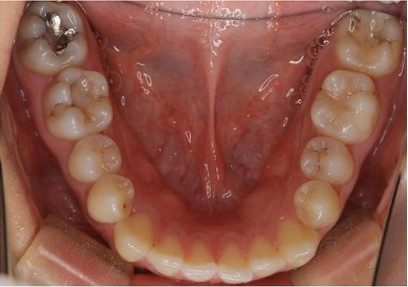

矯正歯科

症例集

ortho_case_1_b2